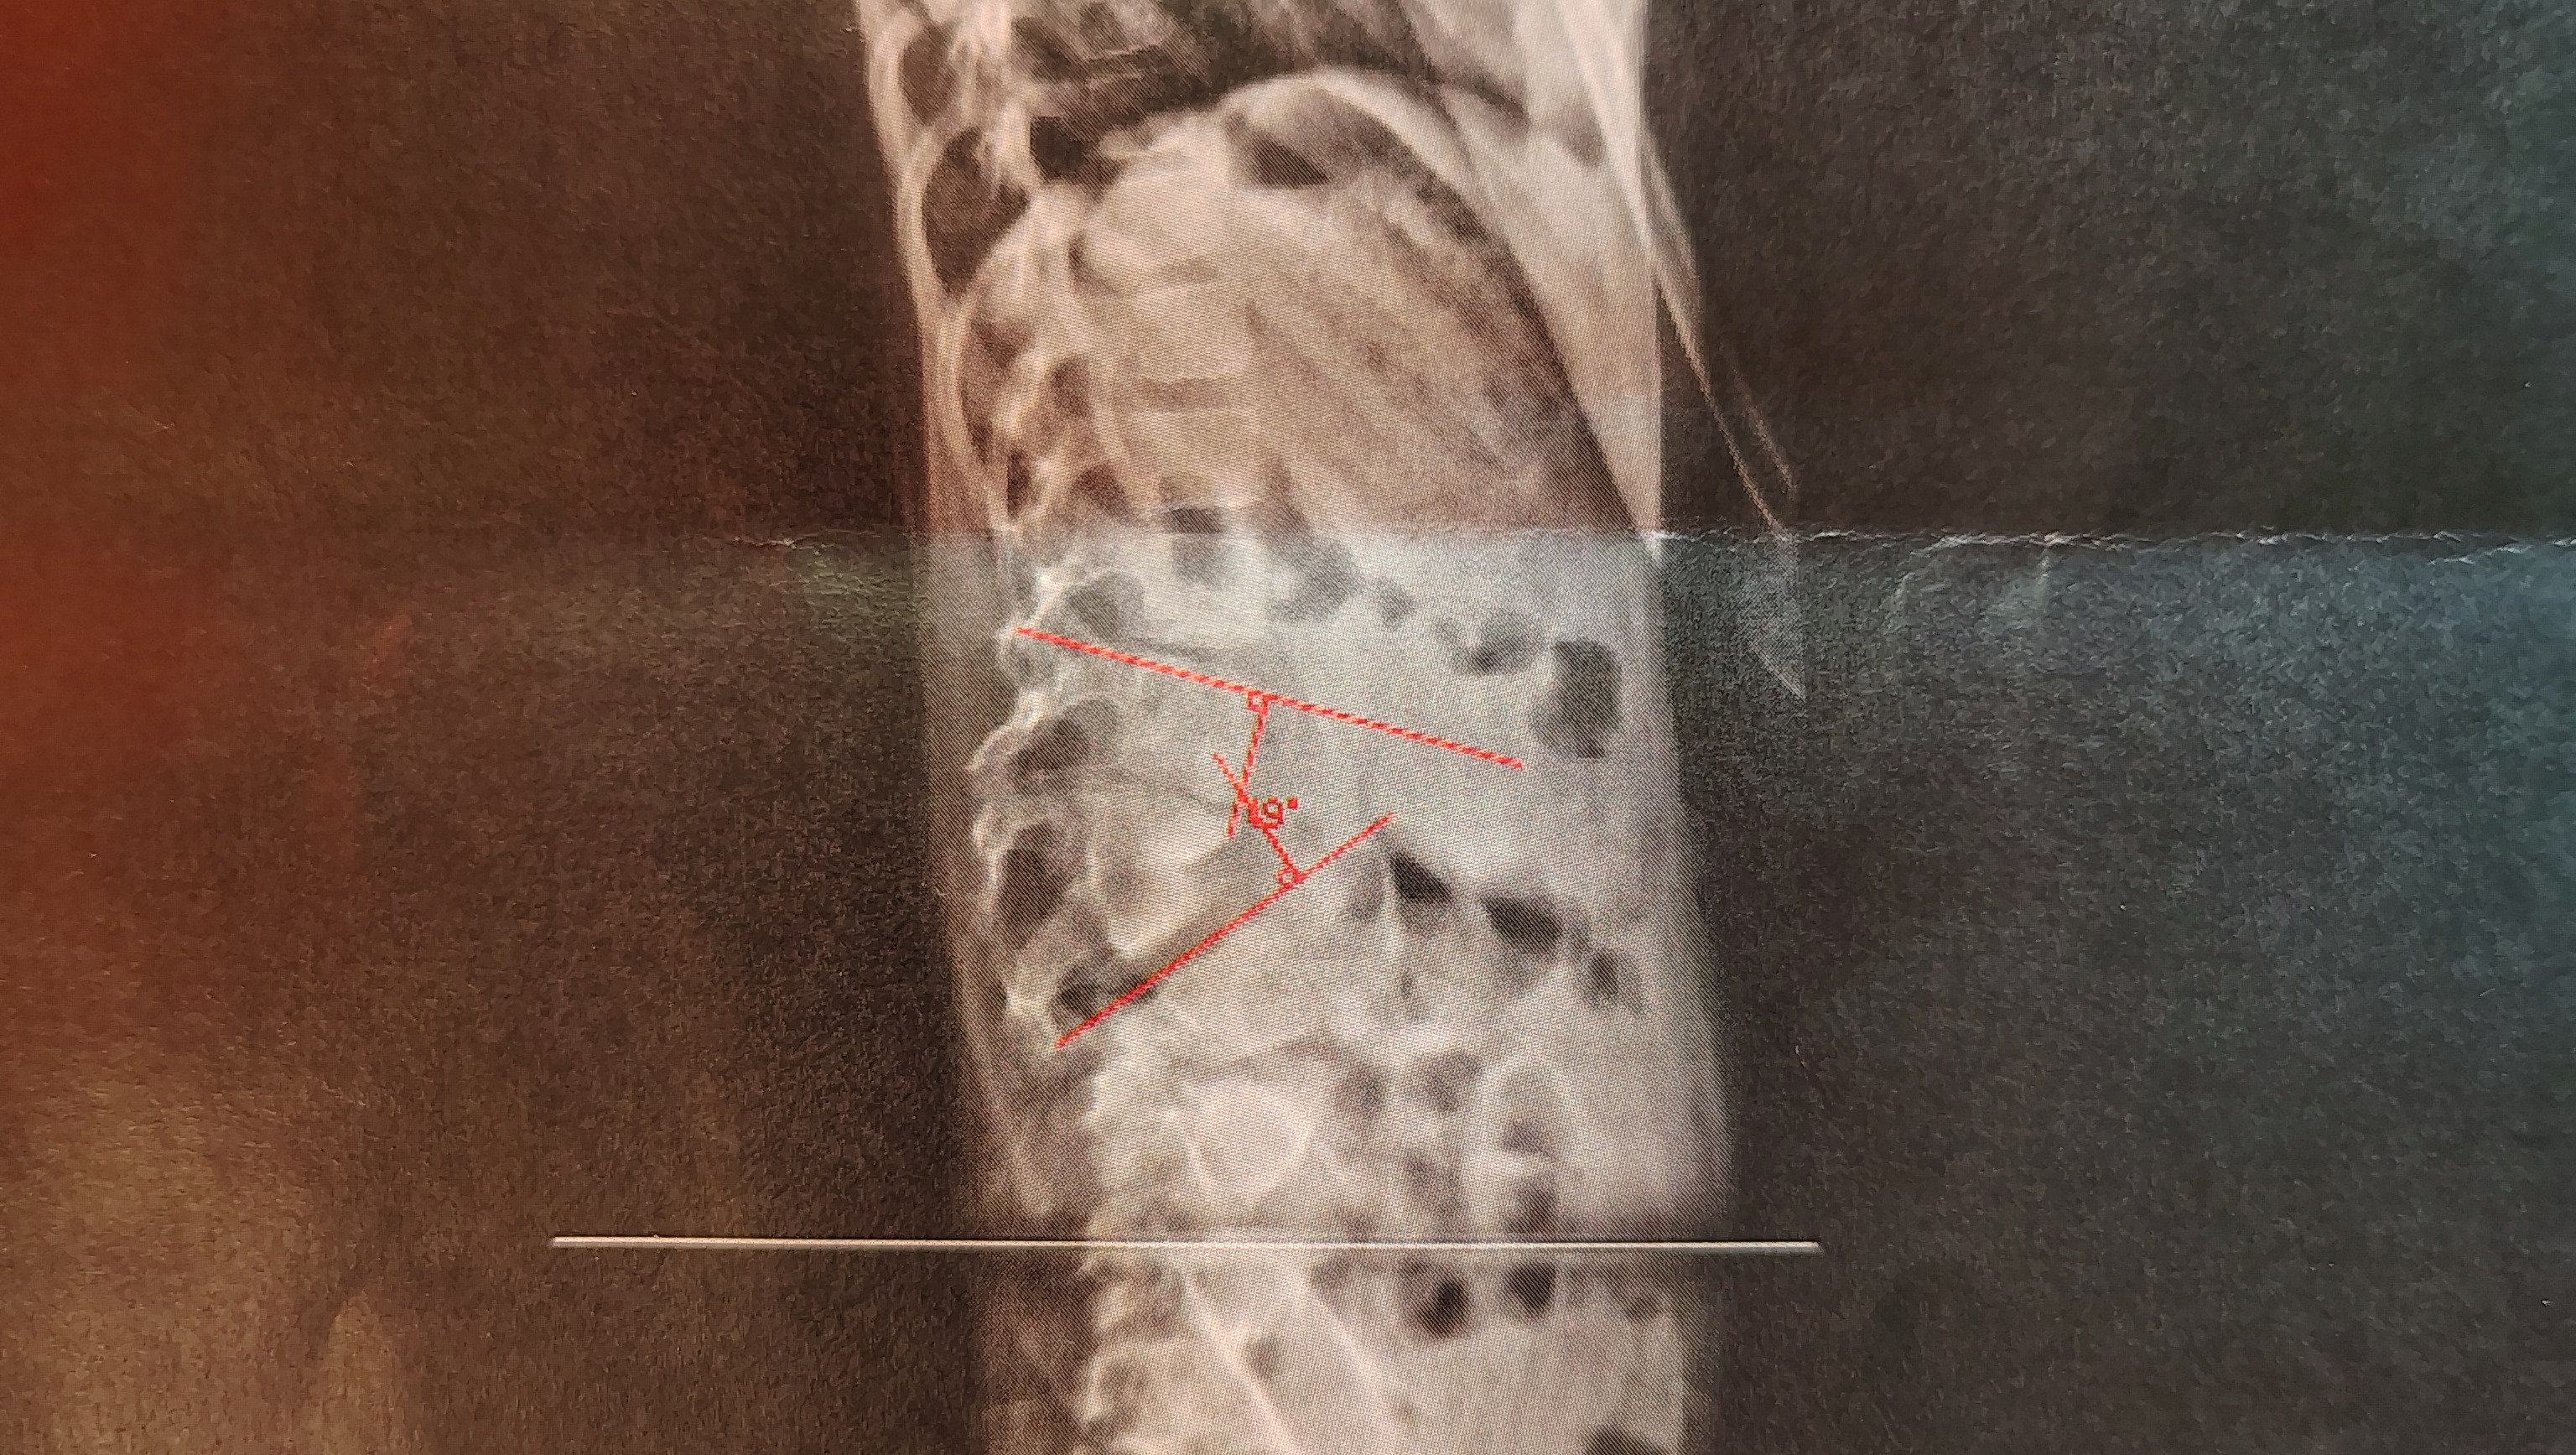

When she was just 2 weeks old, she had her first of the 30 surgeries she has had so far. They had to break her jaw and move it forward so that she could breathe, as her tongue would fall back and cause her to stop breathing. Lily was born with 1 kidney, she has a hemi vertebrae and a butterfly vertebrae, she is also missing her radius in her left arm and missing two fingers, she has extra ribs, and a cleft palate in the roof of her mouth. She also has a Mickey button in her bladder to help her pee, as she needs to be drained every 2 hours or so. Her urethra is inside her vagina; that's something she will also need repaired, and it is an 8-hour surgery. But for now, they are having to deal with a major back surgery that we knew when she was born she would have to have but weren't expecting it to come so quick. Our tilt in our backs is supposed to be at 0; hers is at 49, and just a few months prior, it was at 45, so it's progressing fast. She will go back in about 6 months to have another scan and to talk about planning this surgery that's an all-day thing and a 4-month recovery for her. Physical therapy, etc. This is gonna cause a lot of financial hardships for them with work, etc., and traveling 2 hours away. This is very hard to deal with for all of us, as nobody wants their children to go through these things. It's a very sad and hard thing to think about right now, as she just started school and is flourishing wonderfully. She has made so many friends and is so smart. She has been through a lot these past 6 years; it never gets easier, that's for sure—it gets harder. We know God's got her and is gonna be with her through this all. Please say a prayer for her, and any amount will help. $1 will help. Sharing this will help and be very appreciated, and we are thankful and blessed to have great family and friends through this all. This will help Ricky and Haley A LOT. They will both be missing work. So I wanna look out for them ahead of the game and know they will have everything they may need along the way.

This is a picture of her back and the section they will remove and replace.